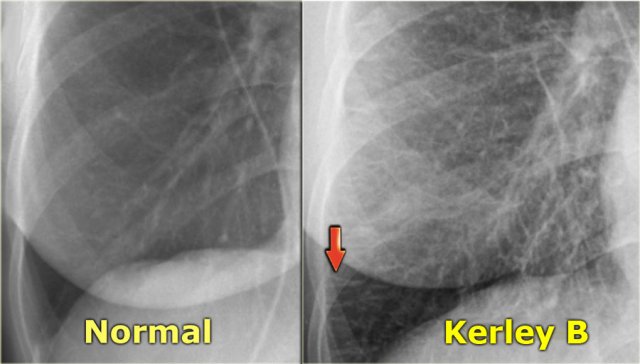

When fluid leaks into the peripheral interlobular septa it is seen as Kerley B or septal lines.

Kerley-B lines are seen as peripheral short 1-2 cm horizontal lines near the costophrenic angles.

These lines run perpendicular to the pleura.